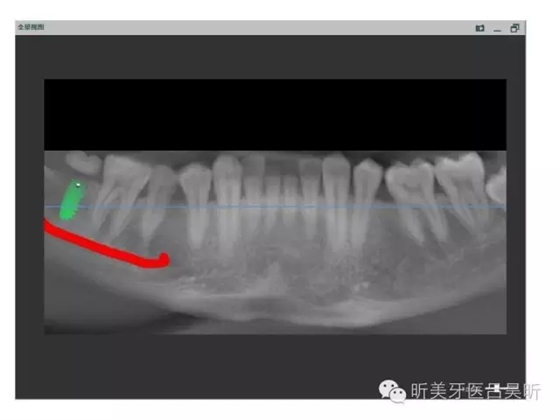

可見種植位點舌側(cè)區(qū)凹陷,牙槽骨上部舌傾明顯。

擬定種植三維方向

以修復(fù)為導(dǎo)向的種植位點設(shè)計